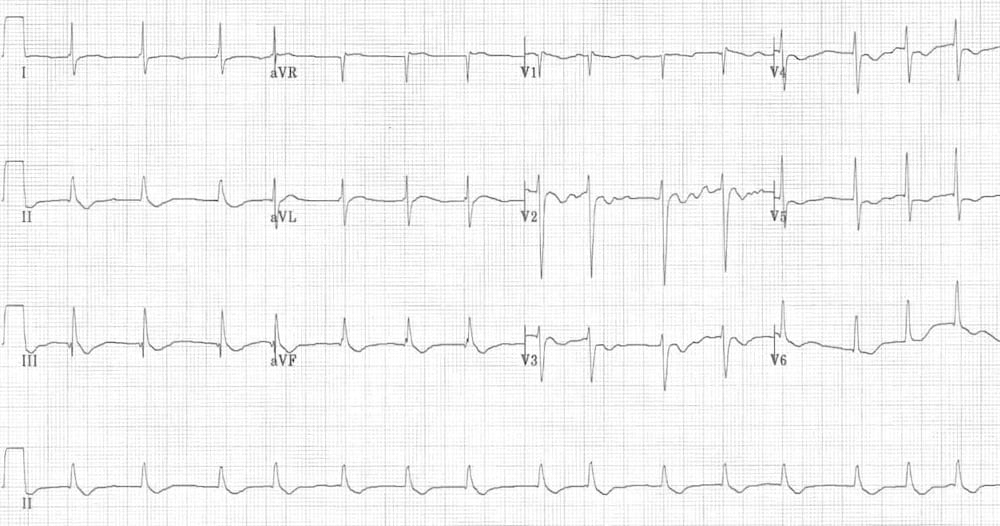

This ECG shows features suggestive of PE. Sinus tachycardia is present (rate 100 bpm). There is clear T wave inversion in right precordial leads (V1-V4) and in inferior leads (II, III, aVF). S1Q3T3 pattern is also present.

https://litfl.com/pulmonary-embolism-ecg-library/

© Life in the Fast Lane. Licensed under CC BY-NC 4.0